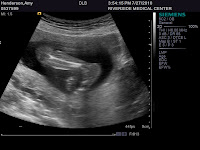

I had my 20-week ultrasound today, and the tech did a great job in not letting me find out the gender--Thanks, Dana. She just so happens to work with Peter in the radiology department at the hospital, so here's hoping she doesn't crack in the next 20 weeks.

(from left to right: Goy's legs and feet, Goy's spine, Goy's face...with open mouth)

I've been measuring (uterus-wise) a little ahead of schedule (in fact a month ago, the doc told me that I'm either measuring 3-4 wks ahead of schedule or there are twins...well I know exactly when my last cycle was and there was no way there were twins in there), but the baby via ultrasound measured right on time. The heart rate is about 140 beats per minute and Goy is weighing in at about 12 ounces at this time. I have gained about 4 lbs so far...and hoping to keep the weight gain around 15-25 pounds max.